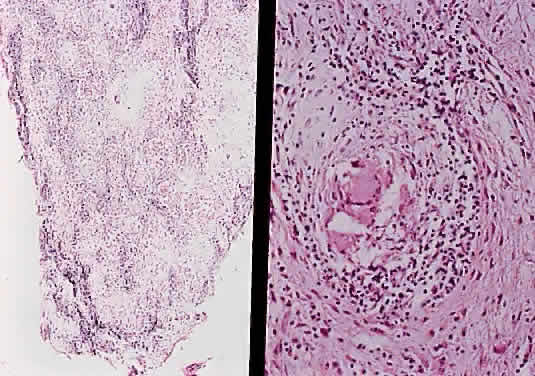

The optic nerve is affected in some manner in 1% to 5% of patients with sarcoidosis and is the second most frequently involved cranial nerve—the facial nerve being the most common.67,68 Rarely, sarcoidosis may present as tumefactive enlargement of the optic nerve without evidence of systemic disease. Most cases are misdiagnosed initially as meningioma or orbital pseudotumor (Figs. 50 and 51).67,69

Fig. 51. Sarcoidosis of the optic nerve. Noncaseating granulomas replace the optic nerve parenchyma (low power, left; high power, right).